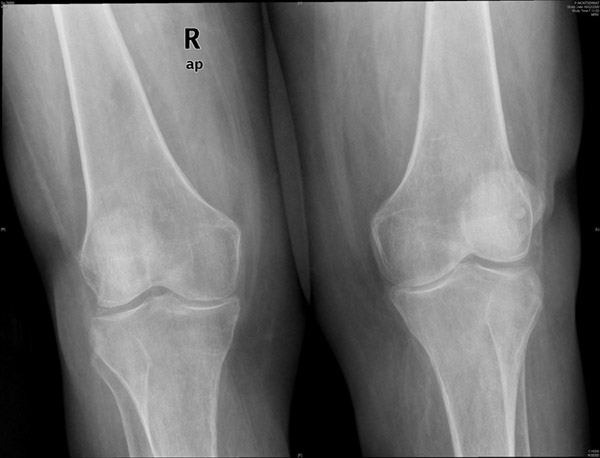

APR Gonartrosis

Desplazamiento de rótulas por genu valgo.

Artrosis femoro-patelar.